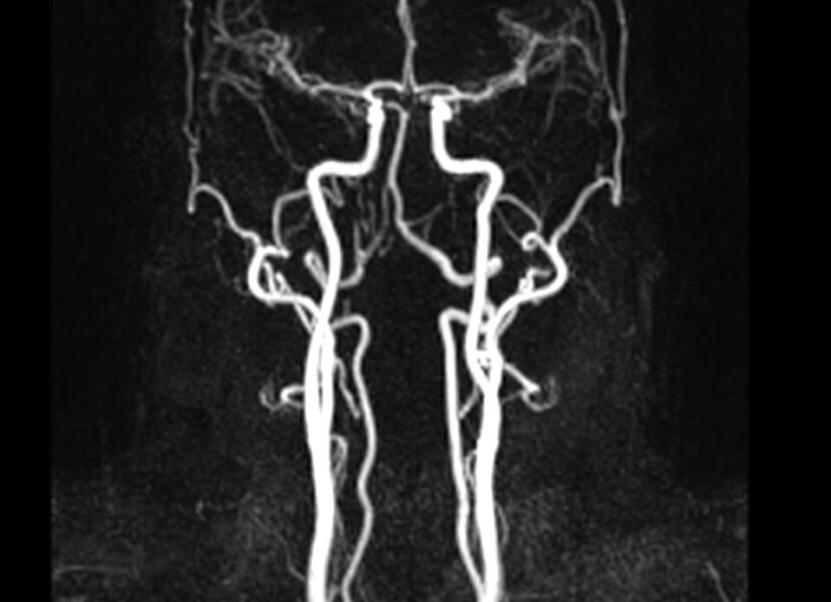

Гормональным сбоем у женщины называется результат воздействия на организм различных факторов, который приводит к нарушению работы гормональной системы на разных ее уровнях. К внешним причинам патологии относятся физические и психологические нагрузки (атмосфера в семейной и профессиональной жизни). К внутренним — состояние здоровья (хронические заболевания ). Определить гормональный сбой у женщины можно с помощью анализа крови.